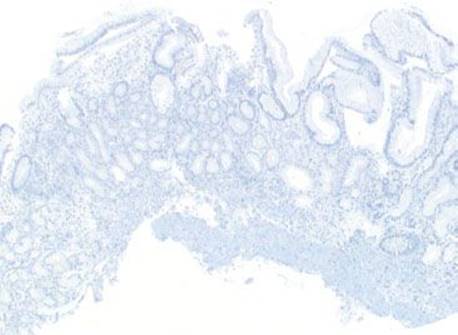

Figure 2.116 Chronic gastritis pattern, lymphoid aggregate subpattern, AMAG. At scanning magnification, a prominent lymphoid aggregate is present in this body biopsy. Given the location of injury and the combination of background intestinal metaplasia and the total lack of oxyntic glands, the etiology is likely AMAG.

Figure 2.117 Chronic gastritis pattern, lymphoid aggregate, AMAG. Another example of prominent lymphoid aggregates at scanning magnification. Although this biopsy is labeled “body”, no oxyntic glands are present.

Figure 2.118 Chronic gastritis pattern, lymphoid aggregate, AMAG (gastrin immunostain). A gastrin immunostain of the previous figure is devoid of G cells, confirming the tissue originated from the gastric body.

Figure 2.119 Chronic gastritis pattern, lymphoid aggregate, AMAG. Higher magnification of previous figure reveals intestinal metaplasia (top bracket), pyloric metaplasia (lower bracket), and total atrophy of oxyntic glands. The findings are strongly suggestive of AMAG.